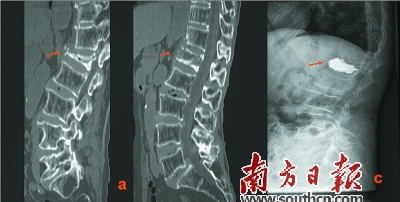

治療前后對比:a為治療前,b為手法復(fù)位后,c為手法復(fù)位+PKP術(shù)后。

康復(fù)科的醫(yī)生梁木榮回憶,他們對吳婆婆感到疼痛難忍的腰背部位進(jìn)行了細(xì)致的檢查,發(fā)現(xiàn)吳婆婆患的是“重度骨質(zhì)疏松性腰1椎體壓縮性骨折”。

所謂“重度骨質(zhì)疏松性腰1椎體壓縮性骨折(壓縮80%)”,通俗點來說,即吳婆婆腰背脊椎的某一節(jié)出現(xiàn)了壓縮性的改變,“由于老年人身體各方面機(jī)能都已在慢慢衰退,老人的腰椎極易出現(xiàn)這樣或那樣的問題,吳婆婆患有的椎體壓縮性骨折,這在老年人群體中很常見”,梁木榮說道。

梁木榮說:“該患者年紀(jì)大、腰椎壓縮程度重,受壓縮的椎節(jié)被壓扁得只剩下1/4,極大地增加了該手術(shù)的難度,很多醫(yī)生都措手無策!倍届厢t(yī)生卻具有豐富的臨床經(jīng)驗,他采取了中西醫(yī)結(jié)合的辦法,先對患病椎體行手法復(fù)位,復(fù)位成功后,再進(jìn)行PKP手術(shù)。